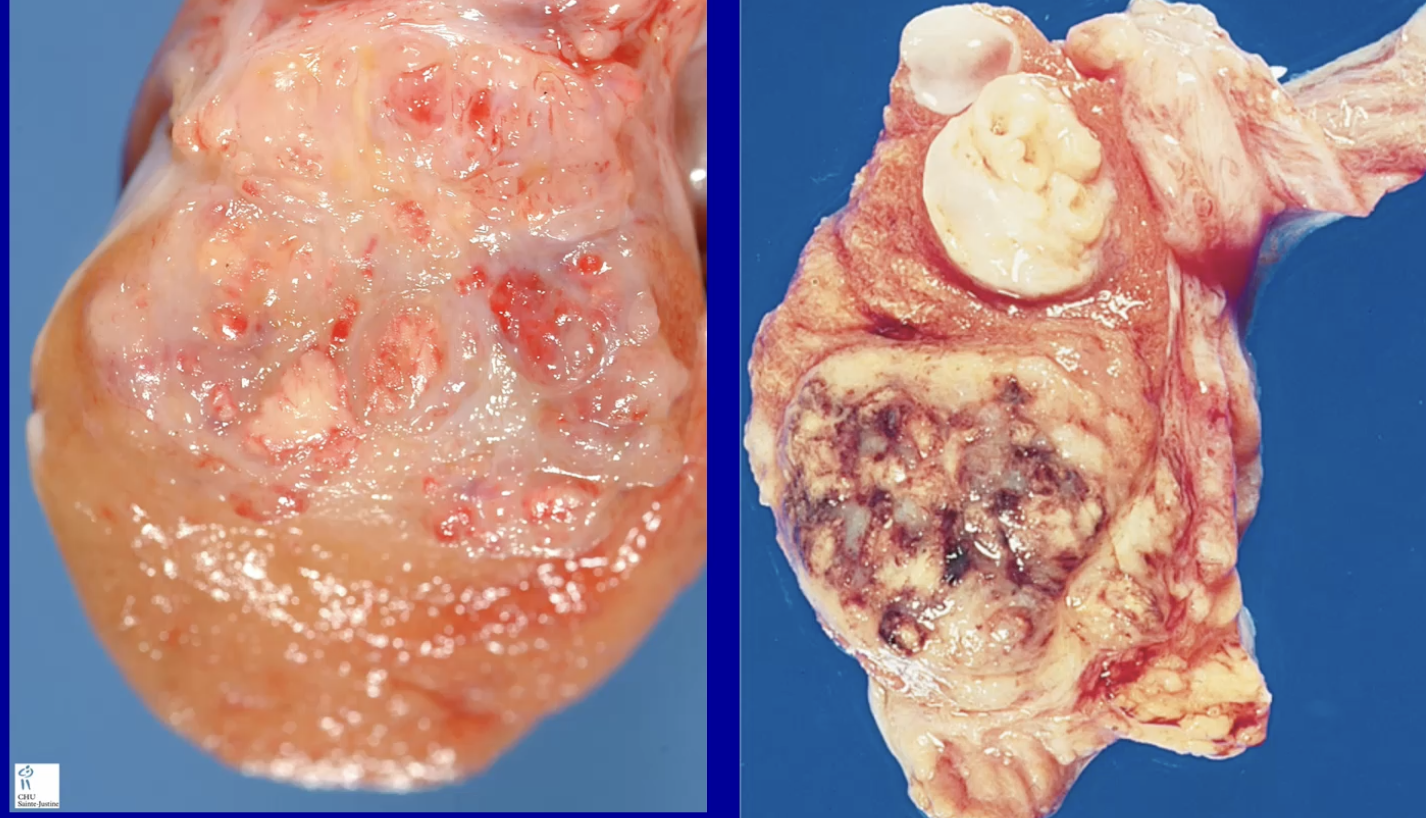

Teratoma

Mature teratoma - better prognosis

Immature teratoma - worse prognosis